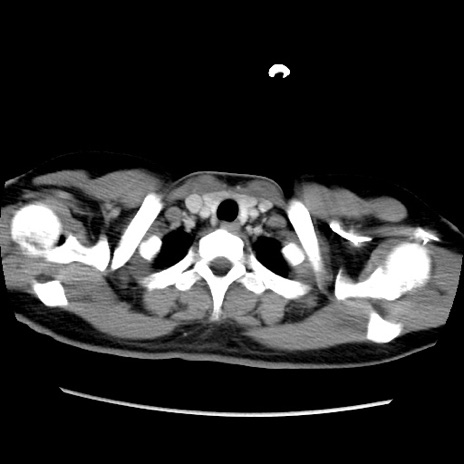

症例39(横断像)

【症例】40歳代女性

【主訴】上下腹部痛

【現病歴】2日目から下腹部痛あり。夜間は痛みで眠れなかった。昨日より上腹部痛と下痢が出現。臥位で痛みは軽快したため、休んでいた。本日になって臥位でも立位でも痛みが強くなってきたため救急要請。

【既往歴】子宮内膜症

【身体所見】部:平坦・軟、左上下腹部に圧痛あり、反跳痛あり。

【データ】WBC 21800、CRP 26.78